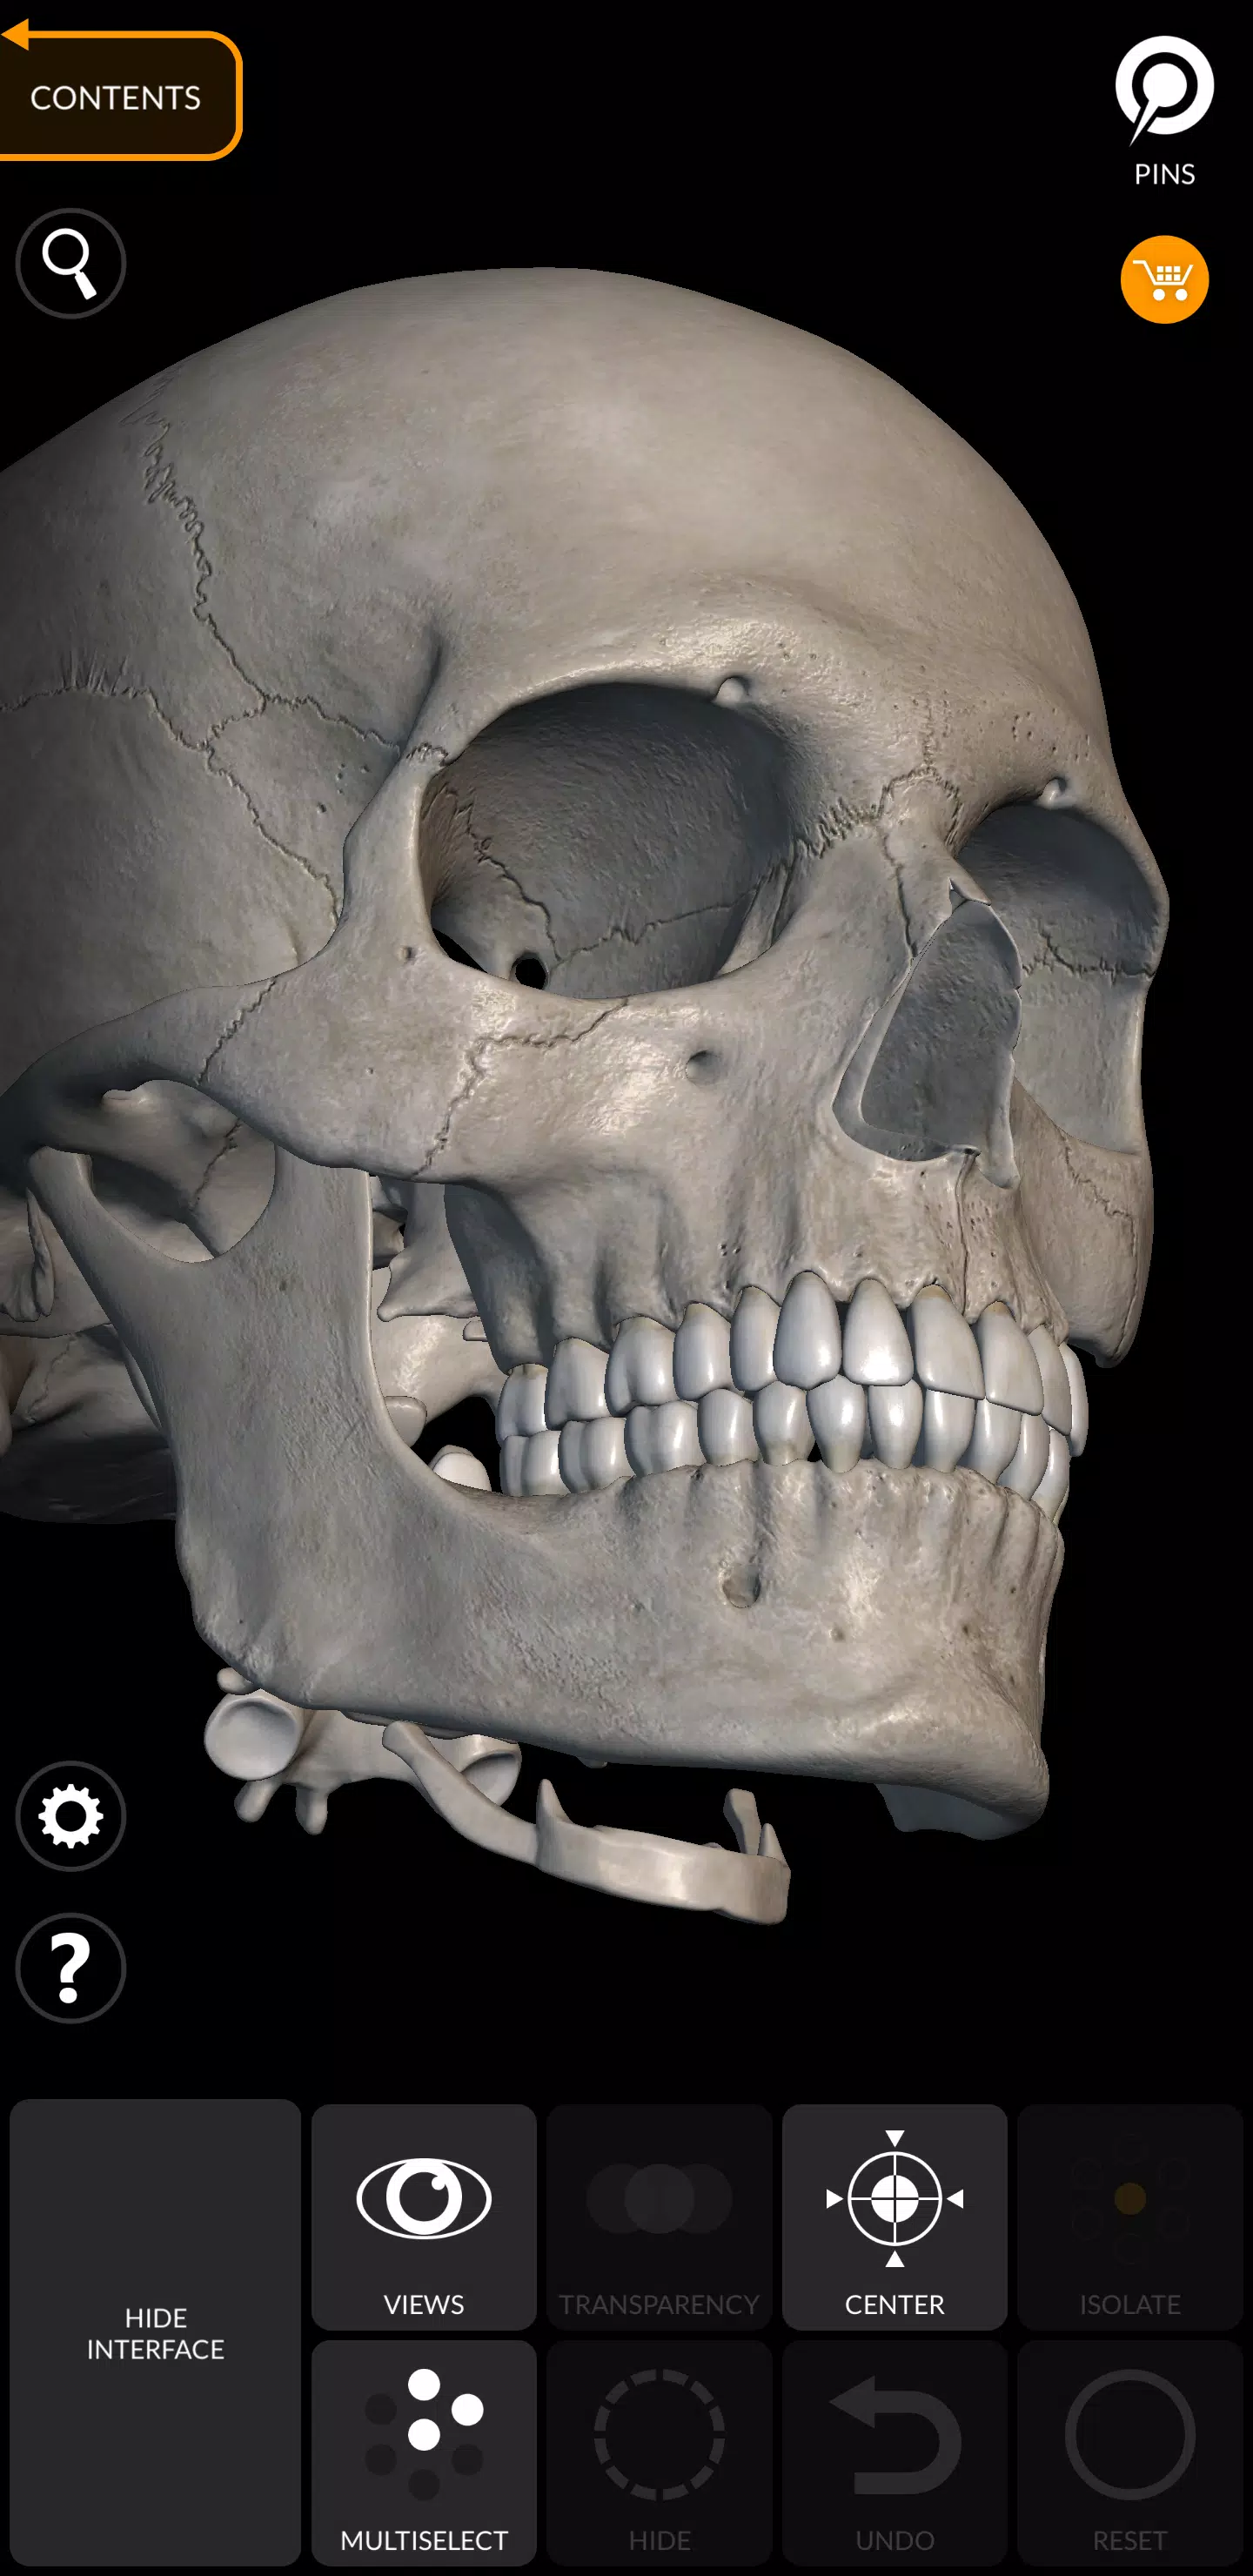

„Szkielet | Atlas 3D anatomii” to najnowocześniejszy atlas anatomii 3D, który zapewnia niezrównane interaktywne doświadczenie z bardzo szczegółowymi modelami anatomicznymi. To narzędzie nowej generacji rewolucjonizuje sposób, w jaki eksplorujesz ludzki szkielet, oferując dogłębną, trójwymiarową perspektywę, która poprawia twoje zrozumienie anatomii szkieletowej.

Każda kość w ludzkim szkielecie została skrupulatnie zrekonstruowana w 3D, co pozwala obracać i powiększać każdy model, aby obserwować skomplikowane szczegóły pod dowolnym kątem. Ten poziom szczegółowości jest idealny zarówno do użytku edukacyjnego, jak i profesjonalnego, oferując kompleksowy obraz struktury szkieletowej.

Aplikacja ma przyjazny dla użytkownika interfejs, w którym można wybrać modele lub piny do wyświetlania terminów związanych z określonymi częściami anatomicznymi. Obsługuje 12 języków, w tym łacina, angielski, francuski, niemiecki, włoski, portugalski, rosyjski, hiszpański, chiński, japoński, koreański i turecki. Możesz nawet wyświetlać jednocześnie terminy anatomiczne w dwóch językach, co czyni go nieocenionym zasobem dla międzynarodowych użytkowników i wielojęzycznych uczniów.

Prosty i intuicyjny interfejs

- Hide/Show Interface: Idealny do użytku na smartfonach dla usprawnionego wrażenia.